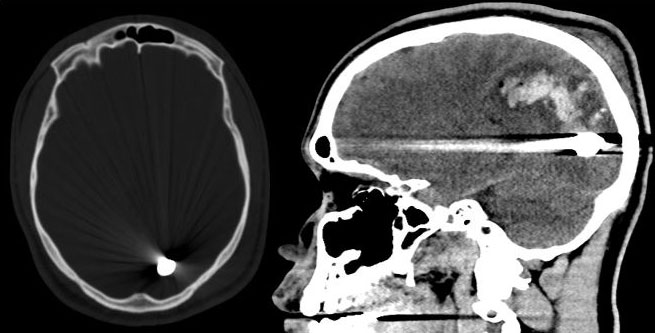

Repeat CT four days later after a single episode of seizure revealed bullet migration posteriorly, likely gravity directed within the injury track in the bed-ridden patient. Within the bullet tract, there is significant interval ballooning of intraparenchymal hemorrhage involving the medial posterior left frontal lobe and left parietal lobe. Three days later (one week after initial injury) the bullet has moved anteriorly appearing next to the left ventricular atrium (Figure 2). Two weeks later on initial follow up the bullet appeared in the anterior margin of the cistern of the lamina terminalis, along the medial surface of the left frontal lobe next to the frontal horn of the left lateral ventricle (Figure 3). Two weeks later (one month after initial injury) the bullet migrated medially and downwards, lodged in the left paramedian anterior cranial fossa floor under the left gyrus rectus, superior to the posterior cribriform plate margin (Figure 4). The patient was conscious with a right hemianopsia but no other eloquent neurologic deficit, even after his single seizure episode. The patient was discharged from the hospital after one month of observation. Surgical intervention was not considered, as the patient displayed no new neurological deficit during the follow-up. He was managed conservatively, no recurrent seizures reported. As he remained asymptomatic, continued conservative observation of this bullet was recommended. However, if he does have symptoms, including visual disturbances or uncontrollable seizures, and the bullet appears to be stable in position, retrieval may be an option in the future if he is symptomatic. He is now doing well and has made a great recovery (Figure 5 and Figure 6).

Figure 2: CT four days later after a single episode of seizure revealed bullet migration posteriorly. Within the bullet tract, there is significant interval ballooning of intraparenchymal hemorrhage involving the medial posterior left frontal lobe and left parietal lobe. View Figure 2

Figure 3: One week CT, the bullet has moved anteriorly appearing next to the left ventricular atrium. A) Axial bone window; B) Sagittal brain window. View Figure 3

Figure 4: Two week CT, the bullet appeared in the anterior margin of the cistern of the lamina terminalis, along the medial surface of the left frontal lobe next to the frontal horn of the left lateral ventricle. A) Axial bone window; B) Sagittal brain window. View Figure 4

Figure 5: One month CT, the bullet migrated medially and downwards, lodged in the left paramedian anterior cranial fossa floor under the left gyrus rectus, superior to the posterior cribriform plate margin A) Axial bone window; B) Sagittal brain window. View Figure 5